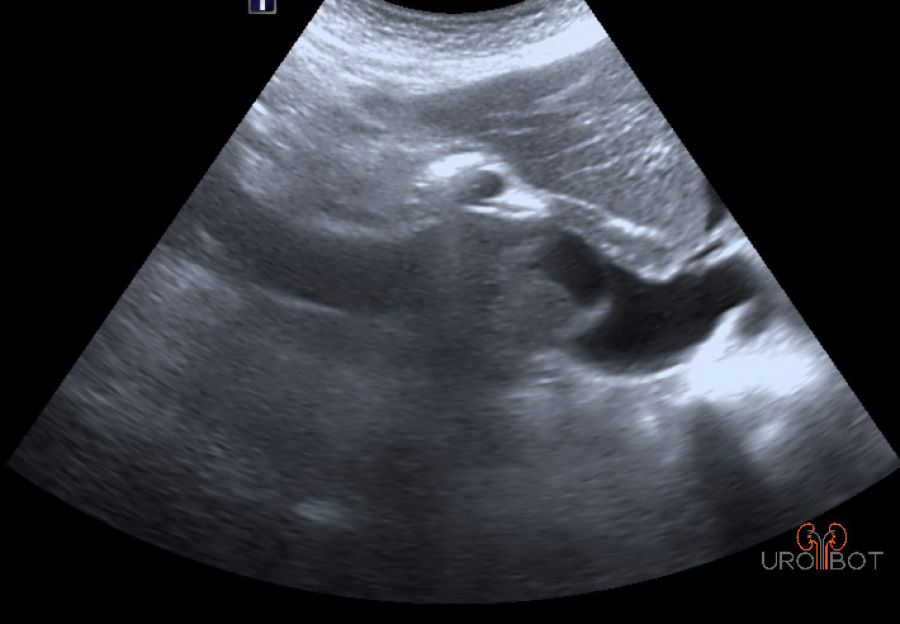

Video Tumorthrombus von Dr. Müller

Das Video zeigt eine sonographische Untersuchung der rechen Seite mit Nachweis eines großen Tumorthrombus in der unteren Hohlvene.